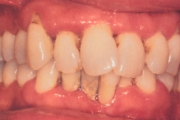

Krooniline parodontiit

Krooniline parodontiit on mikroobide poolt põhjustatud hammaste tugikudede põletik, mille tulemusena tekib progresseeruv alveolaarluu (nähtav röntgenograamil) ja periodontaalligamendi destruktsioon, igemetaskute moodustumine, igeme retsessioon või mõlemad kahjustused kombineeritult. Loe edasi »

Sümptomid:

- igemed veritsevad (19)

- igemed punetavad (21)

- ige on paistes (mädapunn)

- igemed on tursunud/vohavad (17)

- igemed on valulikud (19)

- igemepiir on taandunud (3)